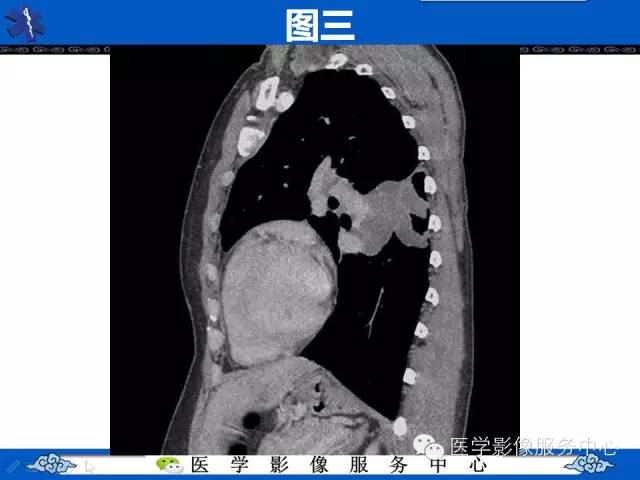

【病例】胸壁弹力纤维瘤1例CT影像表现